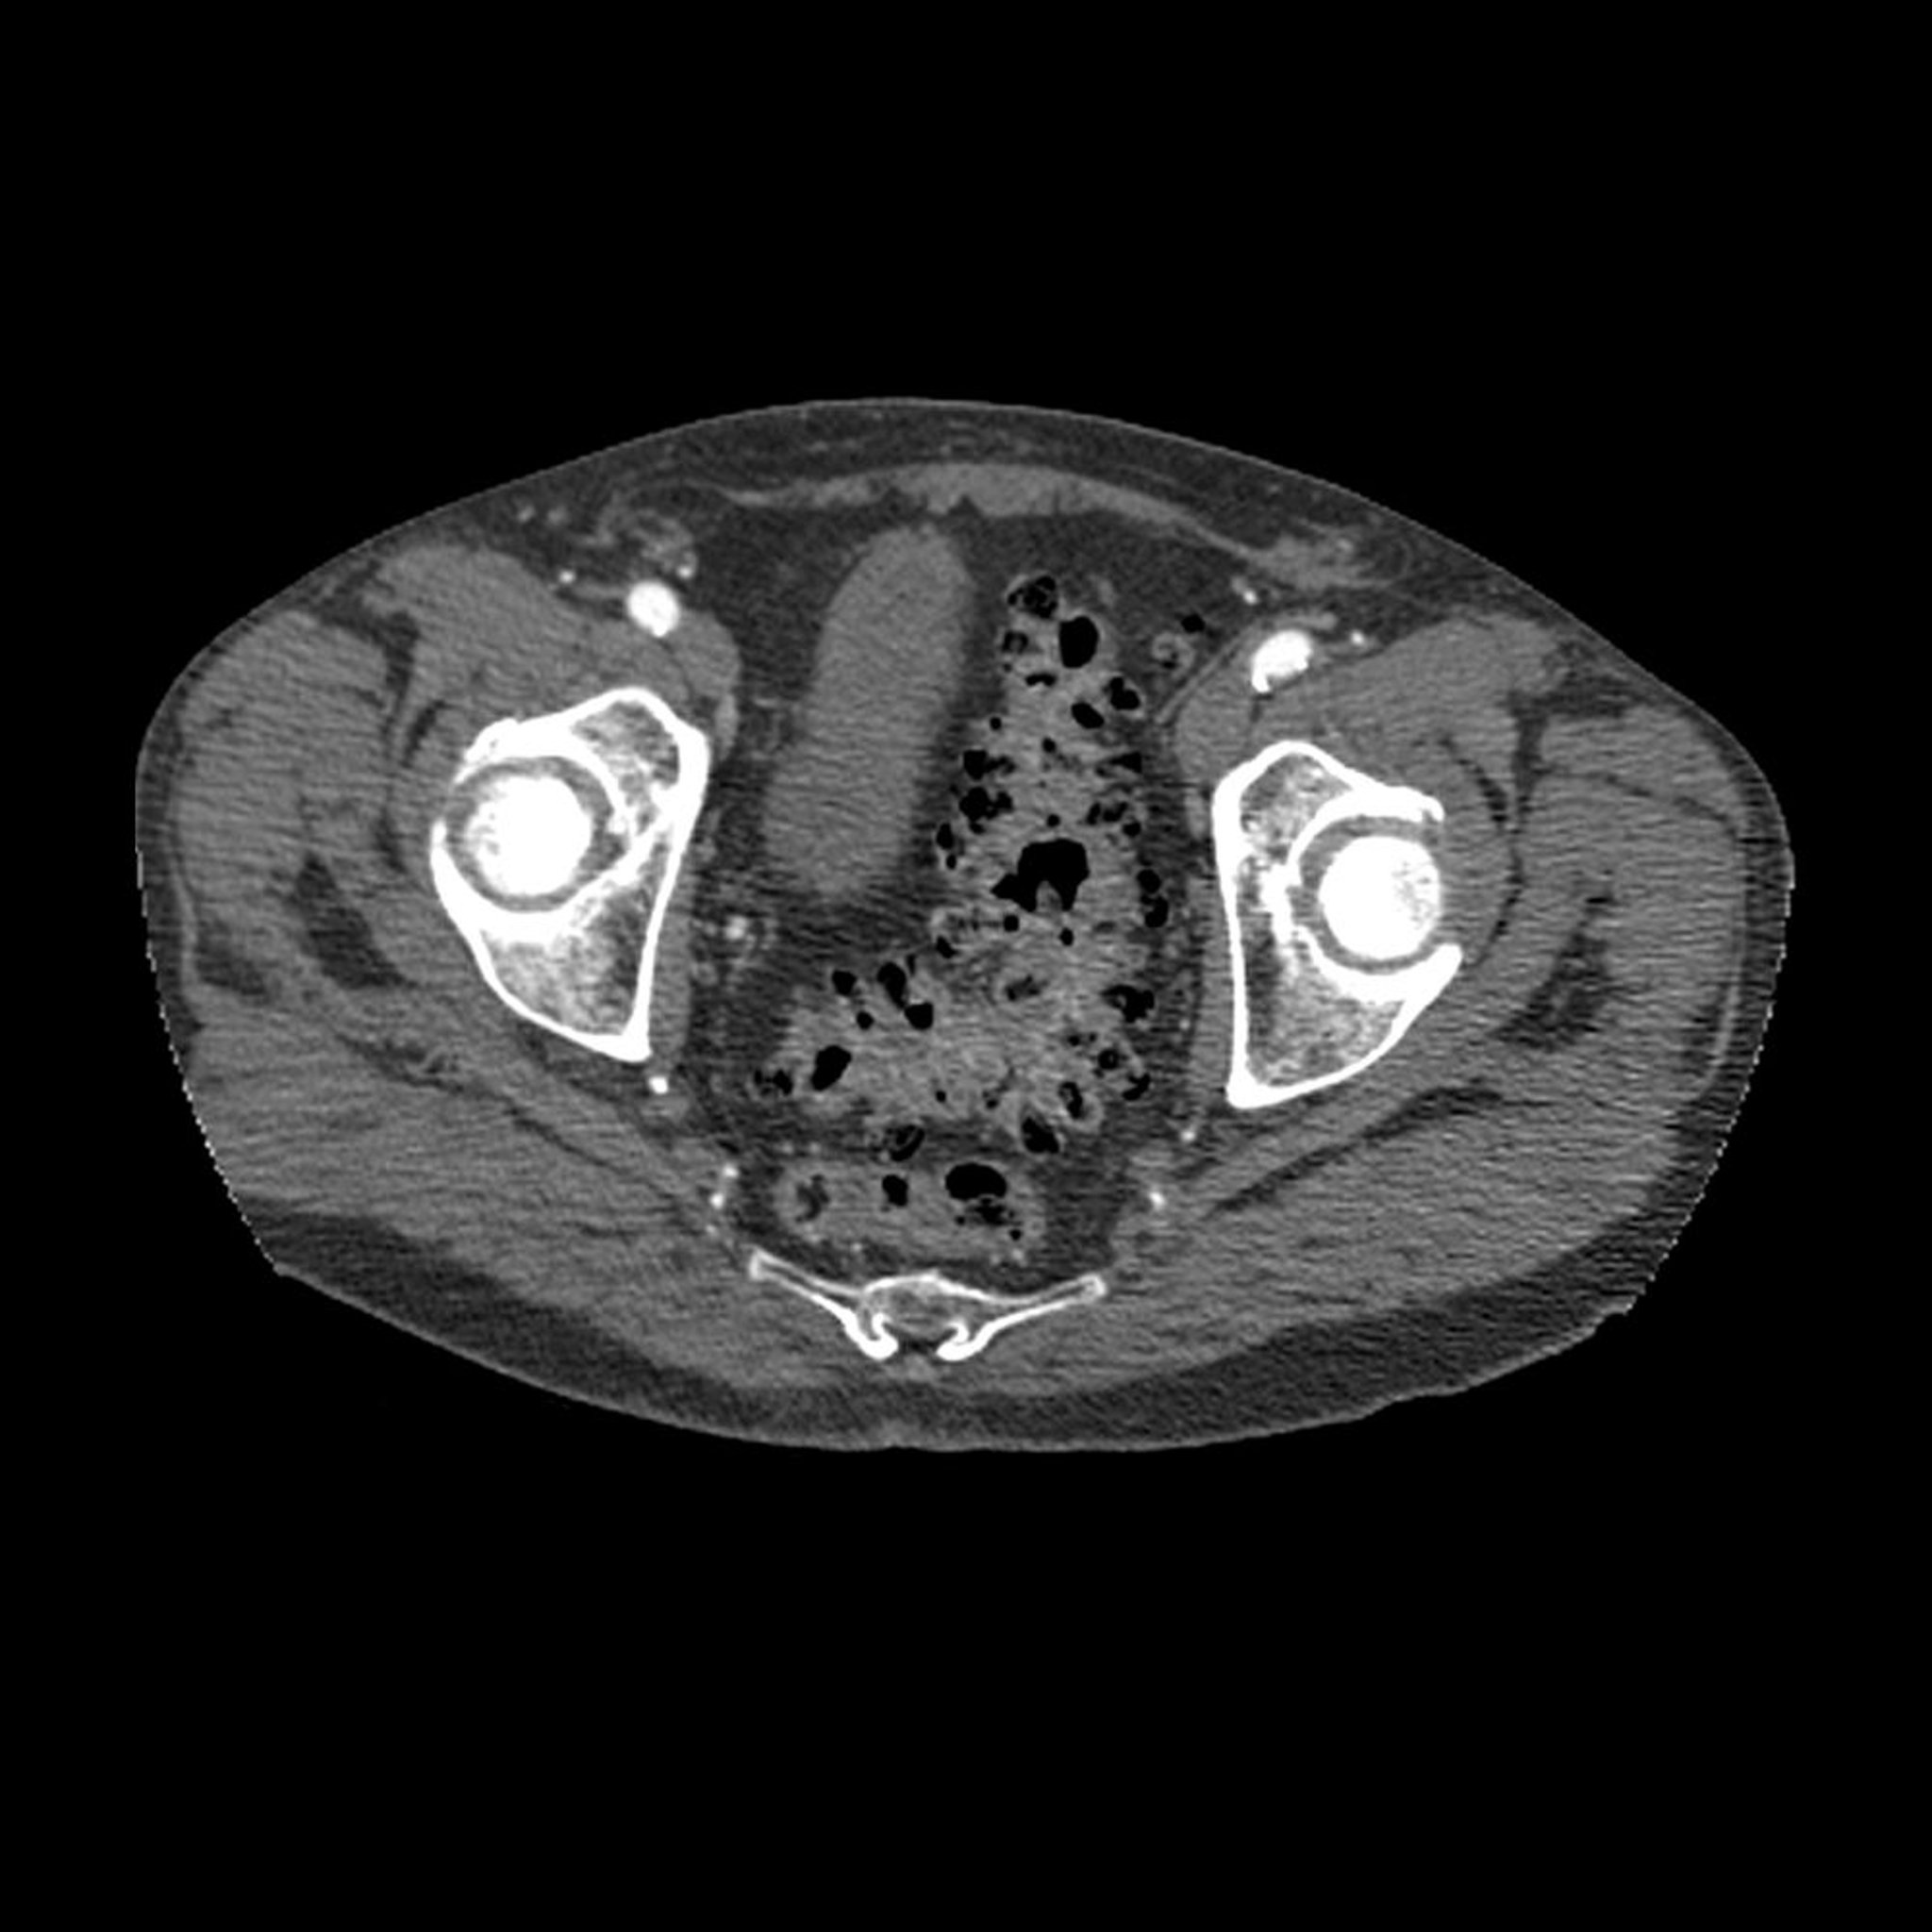

Diverticulose (TDM)

Cette image TDM en coupe axiale à travers le bassin montre l'aspect typique d'une diverticulose (les zones sombres dans la paroi du côlon sigmoïde).